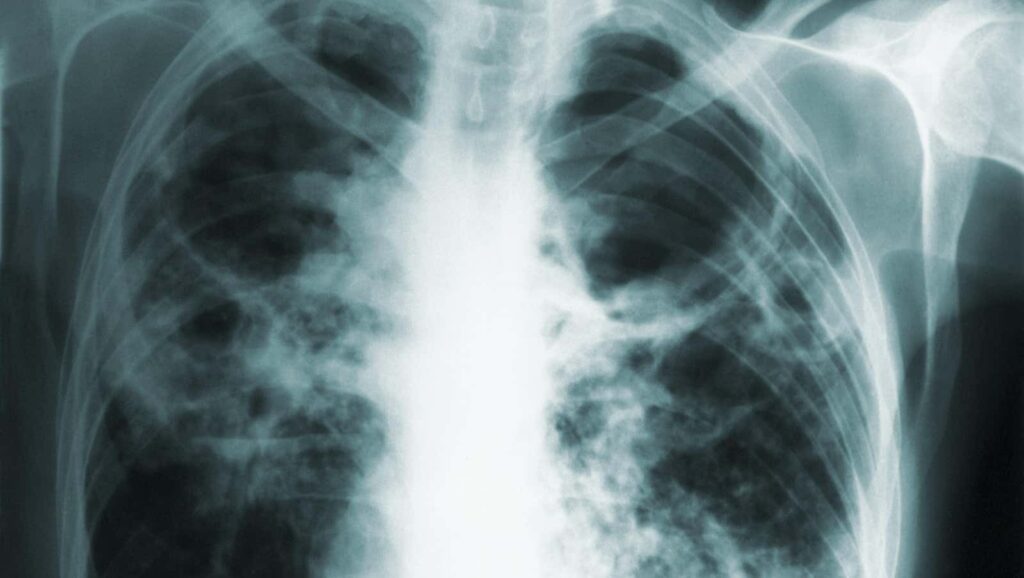

Durante más de un año, una mujer se negó a obedecer las órdenes judiciales de quedarse en casa y expuso a otros a su infección activa de tuberculosis